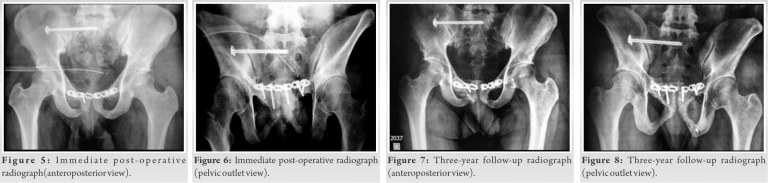

After proper evaluation by the urology, gastric surgery, and anesthesia team, the patient was planned for surgery. After failed initial attempts at closed reduction, the decision to proceed with open reduction was taken. A modified Pfannenstiel incision was made. The insertion of the rectus abdominis muscle was observed to be disrupted along nearly two-thirds of its bony insertion on the right side. The remaining part of the rectus was carefully divided a few millimeters above its insertion on the bone. Then, the cut edges of rectus abdominal muscles were retracted superiorly and the symphysis pubis was exposed subperiosteally. During the procedure, Gamjee pad was inserted posteriorly to protect the bladder and other visceral structures. The right pubis was observed to be incarcerated about 4 cm into the left obturator foramen after having been forced medially and posteriorly. Initial attempts to reduce the pubic symphysis by levering the locked right pubic body out from the left obturator foramen met with failure. Next, external fixator was applied with supra-acetabular Schanz pin placements and the pelvis was gradually distracted to achieve reduction; however, this maneuver also failed. Finally, we opted for a vertical osteotomy of the left superior pubic ramus approximately 2.5 cm from the midline. Lamina spreader was applied into the osteotomy site and it was gradually distracted. Progressively increasing the distraction at the osteotomy site freed the incarcerated right pubic ramus body and it gradually returned back to its normal anatomical position. Post-reduction, the symphysis pubis remained unstable and a 6-hole transpubic recon plate was applied, incorporating the osteotomy site, to achieve stability. The right sacroiliac joint was then stabilized with one 6.5mm × 70mm cannulated partially threaded cancellous screw percutaneously under image intensifier guidance (Fig. 5, 6). The wounds were closed in layers. Care was taken to repair the rectus abdominis insertion, augmented with non-absorbable sutures anchored to the periosteum.

The post-operative period was uneventful. Gluteal sets, TFL stretching, and isometric quadriceps exercises were started from the 2nd post-operative day. Mobilization with partial weight-bearing and strengthening of the rectus was initiated at 8 weeks with progression to full weight-bearing at 3 months. The patient underwent micturating cystourethrogram at 10 weeks followed by penile urethral repair. The fracture healed with no secondary displacement in 3–4 months’ time. He resumed routine activities of daily living at 4 months and sports activities after 6 months. There was breakage of implant and heterotopic ossification in subsequent follow-up; however, the patient did well without any symptoms of hardware breakage and the implant was not removed. At 3-year follow-up (Fig. 7, 8, 9, 10), the patient has not reported any pubic discomfort (osteomyelitis and non-infective osteitis pubis), urinary problems, and/or sexual problems.